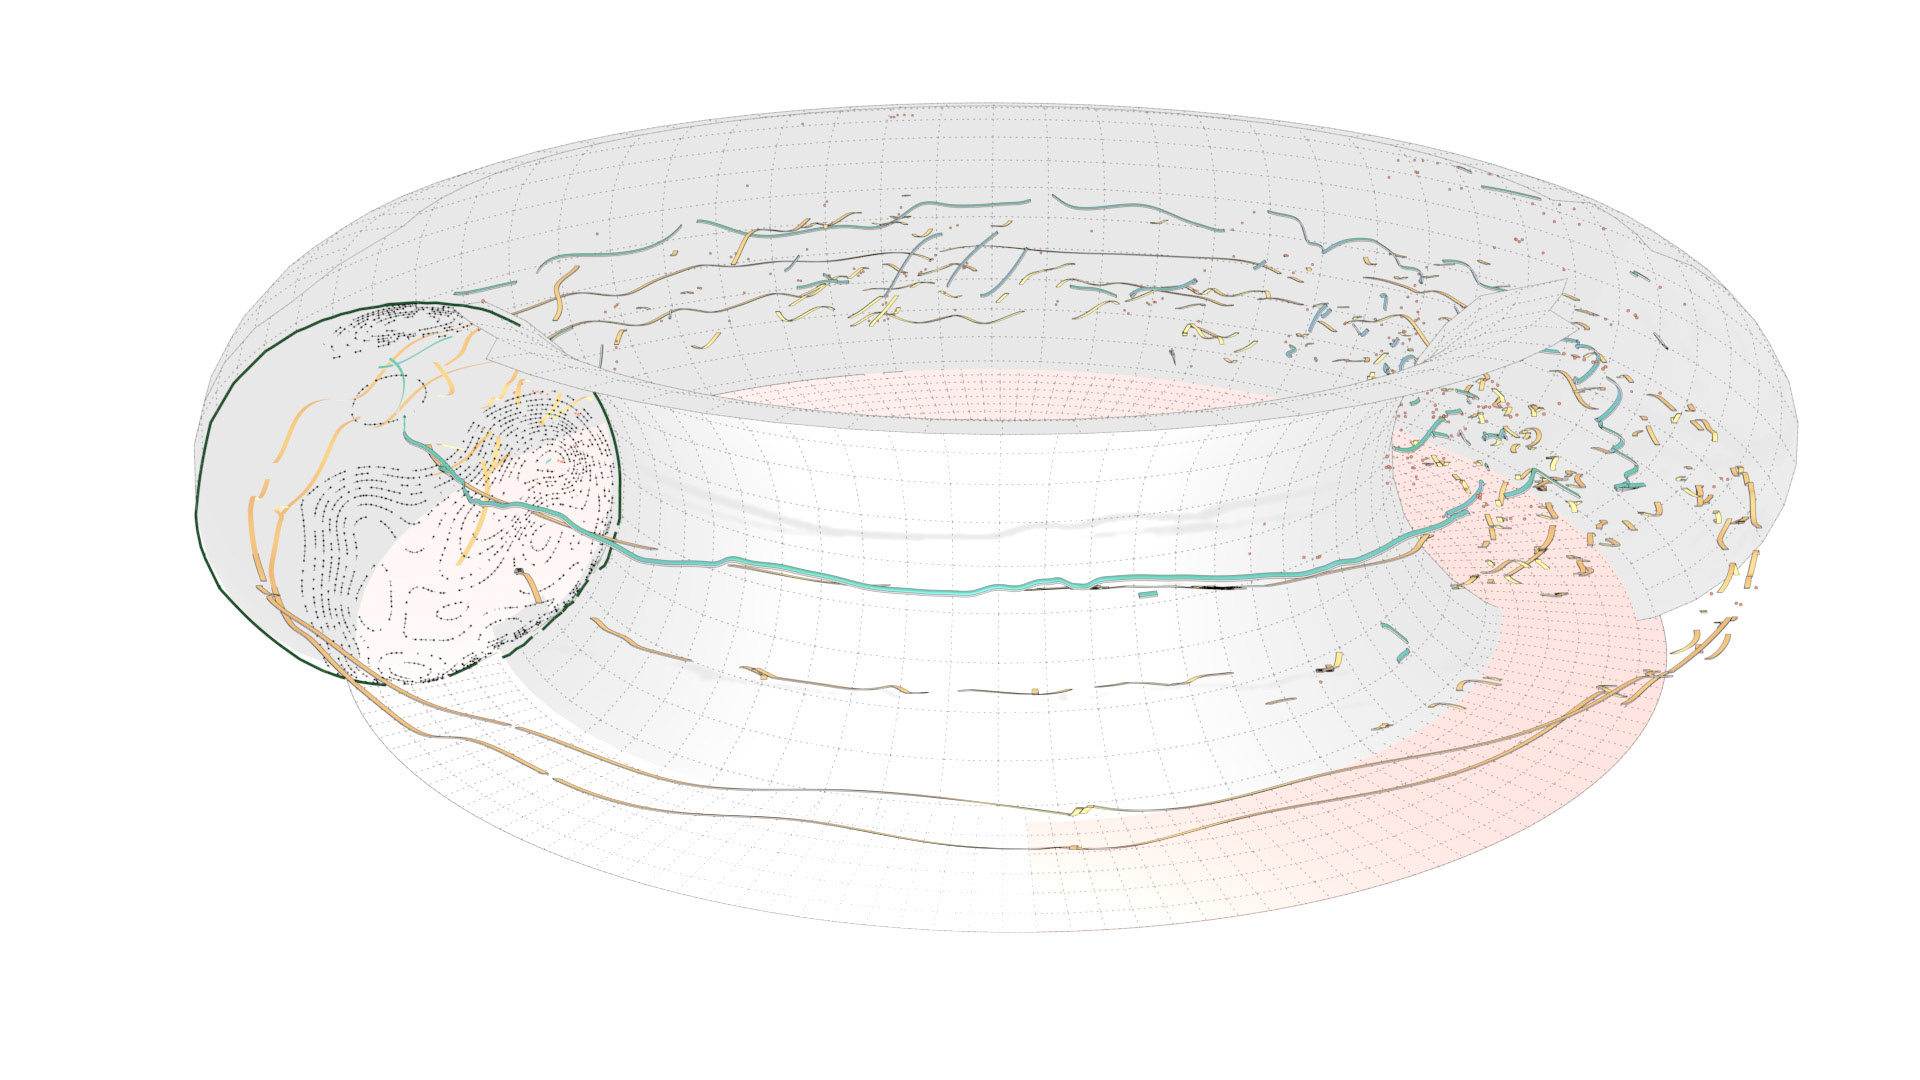

An ongoing collaboration with the Biomedical Simulation Lab (BSL), University of Toronto. In my role, I develop concept sketches and renderings that are then implemented algorithmically. The overall approach is to show turbulent flow visualizations without animation my mapping the transitions among states to carousel that corresponds to the cardiac cycle.